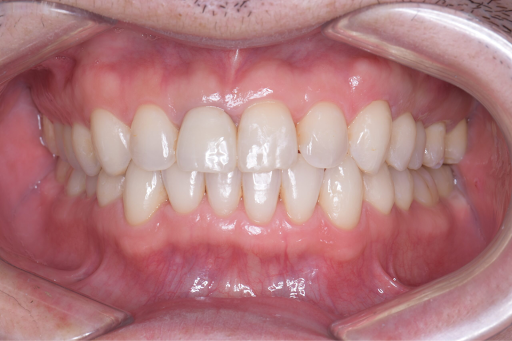

前歯のがたつきを改善するためにインビザラインによる矯正とセラミックインレー、根管治療を行い、金属を使わないメタルフリー治療を実施しました。

見た目と機能の両面で大きく改善している様子がわかります。

<After>